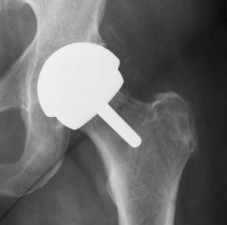

Settlements Announced for Thousands of DePuy Pinnacle Hip Lawsuits

More than 3,000 product liability lawsuits are being resolved with settlement agreements. The claims were filed by plaintiffs who made allegations regarding Johnson & Johnson’s DePuy Pinnacle hip replacements—a metal-on-metal implant linked to a risk of serious complications. A settlement is not an admission of... Read More